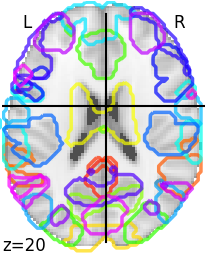

An introduction to fMRI data: the captured signal, the main steps of preprocessing and how functional connectivity is calculated.

The objectives of this module are to: 1) Understand the basis of the signal used in functional magnetic resonance imaging. 2) Know the main steps of preprocessing fMRI data. 3) Know how functional connectivity is calculated, and how it is most commonly used. 4) Know the main brain parcellations and associated technical challenges .